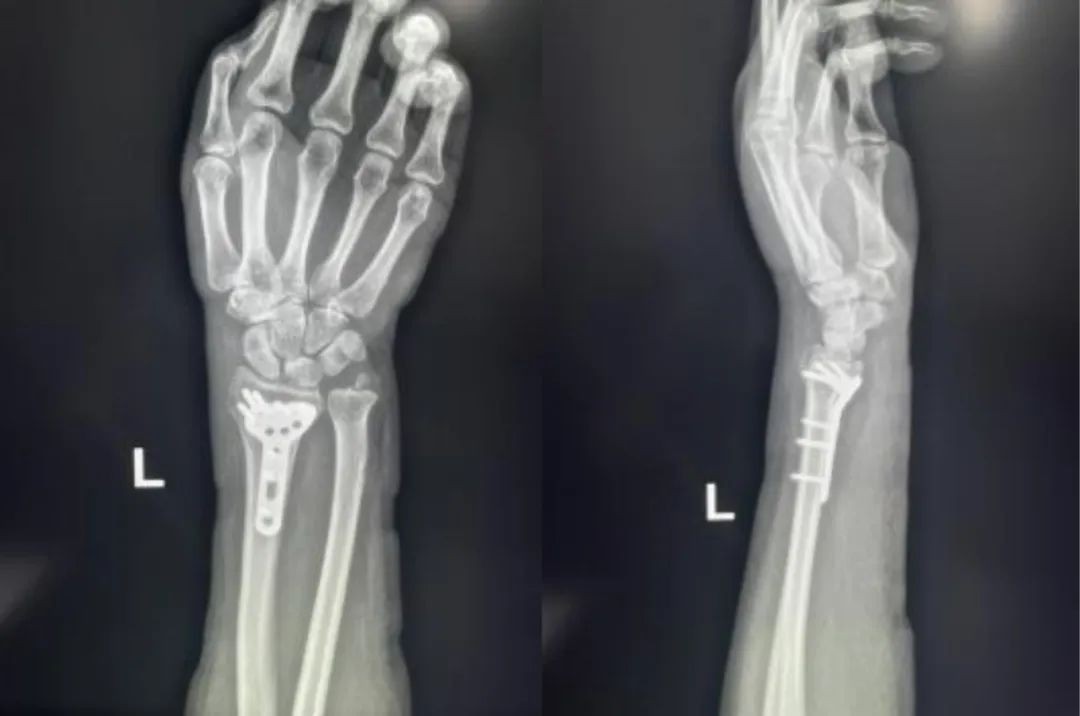

Primer ③